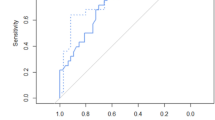

An ROC curve was generated to predict neonatal survival using GA, MRI-derived observed to predicted TLV and % of thorax occupied by liver (Fig. 4). ROC analysis demonstrated an AUC of 0.96 (95% confidence interval [CI]: 0.91, 1.00). ROC curves were also generated to predict survival using observed to predicted TLV only or % of thorax occupied by liver only (Fig. 5). ROC analysis for observed to predicted TLV demonstrated an AUC of 0.80 (95% CI: 0.66, 0.94). ROC analysis for % of thorax occupied by liver demonstrated an AUC of 0.88 (95% CI: 0.77, 0.99). Comparing the three ROC curves demonstrated that a combination of factors (GA, observed to predicted TLV and % of thorax occupied by liver) generated the largest AUC and had the greatest strength of prediction. Multivariable analysis evaluating observed to predicted TLV, % of thorax occupied by liver and GA at the time of MRI exam demonstrated significant differences between survivors and non-survivors (Fig. 6).

The receiver operator characteristic (ROC) curve predicts neonatal survival using gestational age, MRI-derived observed to predicted total lung volume (TLV) and percentage of thorax occupied by liver. ROC analysis demonstrates the value of using observed to predicted TLV, percentage of thorax occupied by liver and gestational age at the time of the exam in predicting survival in isolated congenital diaphragmatic hernia. AUC area under the curve, CI confidence interval, GA gestational age

Receiver operator characteristic (ROC) curves compare a combination of factors with observed to predicted total lung volume (TLV) alone or percentage of thorax occupied by liver alone. ROC analysis demonstrates that a combination of factors generated the largest area under the curve (AUC) with the greatest strength of prediction. Ninety-five percent confidence intervals are given in parentheses. GA gestational age